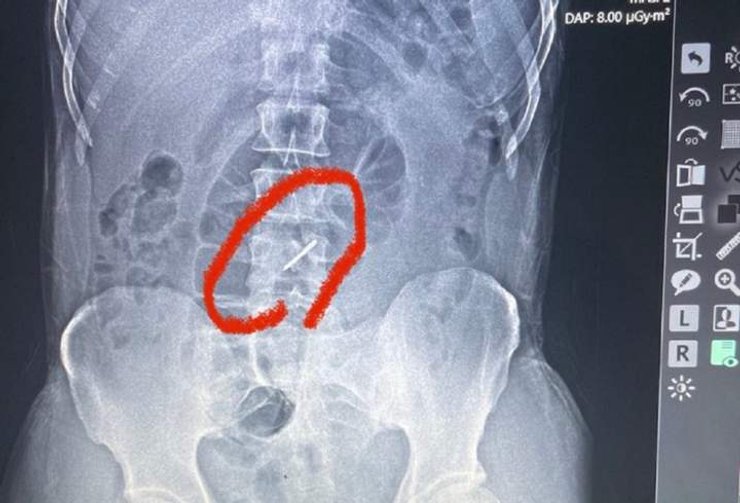

"Стрелка" от кассетного боеприпаса сломала 44-летнему бойцу два поясничных позвонка и застряла в позвоночнике. Но военный обратился к медикам из-за высокой температуры.

Как рассказывают журналисты, во время одного из обстрелов "стрелка" от кассетного боеприпаса сломала мужчине два поясничных позвонка и застряла в позвоночнике. Однако боец (имя которого не называют в целях безопасности) не заметил этого. В госпиталь он обратился лишь тогда, когда боль в пояснице стала действительно его донимать, а температура поднялась до 39 градусов. Медикам мужчина сказал, что у него, наверное, радикулит.

По словам врача военно-полевого госпиталя, львовского сосудистого хирурга Тараса Кобзы, военного направили на рентген, после чего и обнаружились причина его болей в пояснице.

"Во время обстрела элемент кассетной бомбы попал в левое подреберье, сломал два позвонка в поясничном отделе и застрял в позвоночнике", – объяснил врач.

"Стрелку" кассетного боеприпаса медики обнаружили уже во время рентгена.

Как говорит Кобза, обломки сломанных позвонков могли повредить нервы и сосуды, но, к счастью, этого не произошло. Сам мужчина подчеркнул, что даже не подозревал о "стрелке", застрявшей в позвоночнике.

В данном случае "стрелка" попала бойцу в подреберье, где у него есть несколько родинок. Прокол кожи оказался всего около 1 мм, так что военный его даже не заметил, подумал, что это лишь одна из родинок.